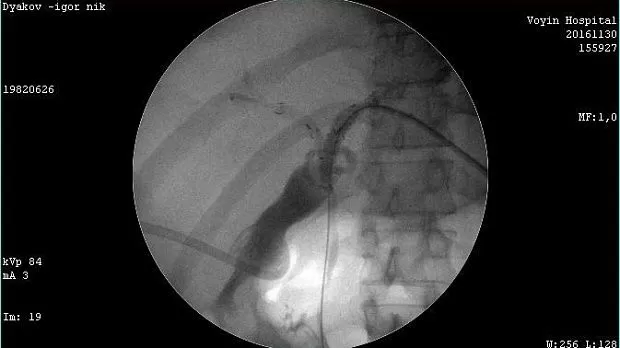

Молодой человек 33 г. Диагноз подтвержден. Стентирован пластиковыми стентами, потом самораскрывающимися. Одномоментно анте и ретроградно - с хорошим результатом. Дальше был поставлен в очередь на трансплантацию. Дальнейшая судьба не известна.